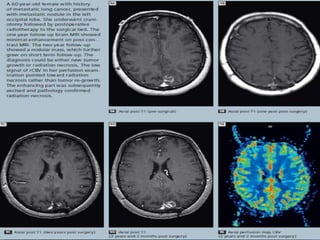

Radiation necrosis. A) Axial T1-weighted

image (TR 450, TE 20, NEX 1, 0.2 mmol/Kg

gadolinium at 5 cc/s) obtained 18 months

following resection of an anaplastic

oligoastrocytoma shows an enhancing

abnormality posterior to the deep margin

of the resection cavity. B) FDG-PET shows

subtle foci of increased glucose

metabolism corresponding to the foci of

enhancement, greater than the adjacent

white matter but less than adjacent grey

matter. This was felt to represent tumor

recurrence by the interpreting PET

specialist. C) Corrected CBV revealed

reduced blood volume within the lesion

(arrow), consistent with radiation necrosis

(perfusion raw data obtained at TR 500,

TE 65, 5-mm thick, 6-mm skip, 0.2

mmol/Kg gadolinium at 5 cc/s). Resection

of the abnormality confirmed radiation

effect without evidence of tumor.